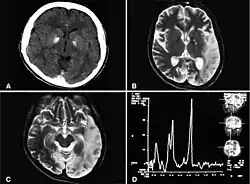

| Basal ganglia calcification, cerebellar atrophy, increased lactate; a CT image of a person diagnosed with MELAS | |

Magnetic-resonance imaging (MRI) is a common imaging test used to identify the presence of stroke-like lesions. These lesions are multifocal infarct-like areas of cortical edema in different stages of ischemic evolution, yet do not commonly conform to any known vascular territory, distinguishing them from a stroke. Initial lesions often occur in the occipital or parietal lobes with eventual involvement of the cerebellum, cerebral cortex, basal ganglia, and thalamus.[15] The occipital lobe is thought to be a region prone to stroke-like lesions due to the high energy requirements of the visual cortex.[16]

Lactate levels are often elevated in serum and cerebrospinal fluid. Magnetic resonance spectroscopy (MRS) may show an elevated lactate peak in affected and even unaffected brain areas. Muscle biopsy shows ragged red fibers. However, genetic evaluation should be done first, which eliminates the need for muscle biopsy in most cases. Diagnosis may be molecular or clinical:[11]